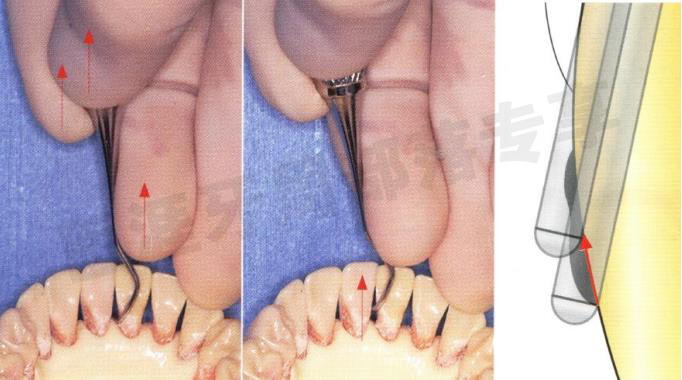

STEP 1

尽量使刃的内侧与根面贴合,减少插入的幅度。这样刃的尾部就能与牙齿角落区的弯角相贴合,插入时不对牙龈产生负担。这时确认从尾部至尖端所有的刃面是否都与牙面贴合。

怎么选洁牙器械5个要点带你学习器械洁牙_https://www.jmylbn.com_新闻资讯_第27张

STEP 2

以刃尾部为中心,保持刃与牙面的贴合,将刃的尖端缓慢下降。

怎么选洁牙器械5个要点带你学习器械洁牙_https://www.jmylbn.com_新闻资讯_第28张

STEP 3

确认尖端至尾部是否保持与牙面的紧密贴合,然后插入牙周袋底。

怎么选洁牙器械5个要点带你学习器械洁牙_https://www.jmylbn.com_新闻资讯_第29张

STEP 4

在插入牙周袋的同时,慢慢提起第一工作弯。使内侧作业角度呈70°,此时第一工作弯与牙面呈20°的夹角。

怎么选洁牙器械5个要点带你学习器械洁牙_https://www.jmylbn.com_新闻资讯_第30张